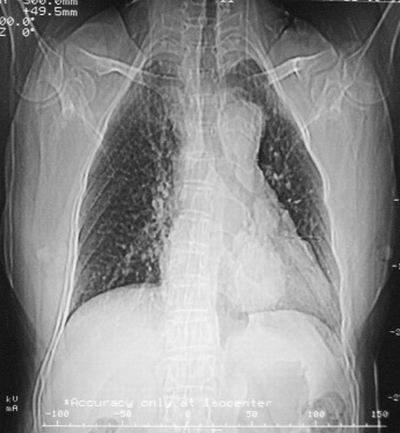

术前(4年前)胸部dr报告书

表现:胸廓左右对称,气管居中,两肺野纹理增多,左下肺见一高密度影,周围见纤维条索影,心影及肺门无增大,双肋膈角锐利,横膈未见异常。

诊断:建议ct检查、随访。